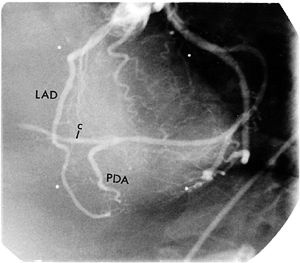

The ascending aorta gives off the right and left coronary arteries. The right coronary artery arises from the right aortic sinus and travels through the coronary groove; its major branches are the sinuatrial nodal artery, the right marginal branch, the posterior interventricular branch, and the atrioventricular nodal artery. The right coronary artery supplies the right atrium, right ventricle, interventricular septum, SA and AV nodes, AV bundles, and parts of the left atrium and ventricle.

The left coronary artery divides into the anterior interventricular (left anterior descending or LAD) branch and a circumflex branch. The former supplies both ventricles as well as most of the interventricular septum. The circumflex branch supplies the left atrium, left heart surface, and the inferior base of the left ventricle, and it gives off a marginal branch.- Why is pain related to myocardial ischemia often "referred"?

Right coronary artery posteriorly, and the left coronary artery anteriorly.- What does the left anterior descending (LAD or anterior interventricular) coronary artery supply?

Anterior wall, septum and the anterolateral wall.- What branches come off the LAD?

Diagonals and septal perforators.Moore's Clinical Anatomy 4th Edition pp. 120-142.